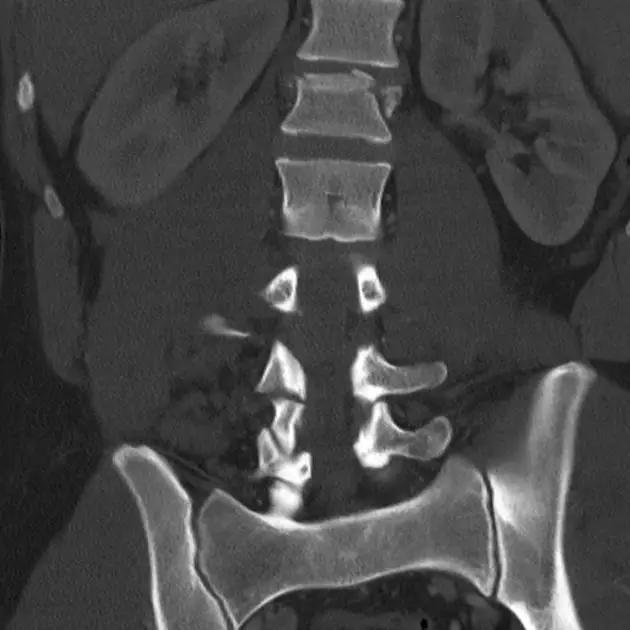

6. Jefferson 骨折

寰椎环的压缩性骨折,骨折是由枢椎压缩性外力引起,骨折多发生在寰椎前侧后侧以及侧方小关节。

第一颈椎双侧性前、后弓骨折,X 线片上很难发现骨折线,有时在正位片上看到 C1 关节突双侧性向外移位,侧位片上看到寰椎前后径增宽及椎前软组织肿胀阴影,CT 检查最为清楚,而 MRI 检查智能显示脊髓损伤情况。

A 图是稳定的 Jefferson 骨折(横韧带完整)轴位像。B 图是不稳定的 Jefferson 骨折(横韧带撕裂)轴位像